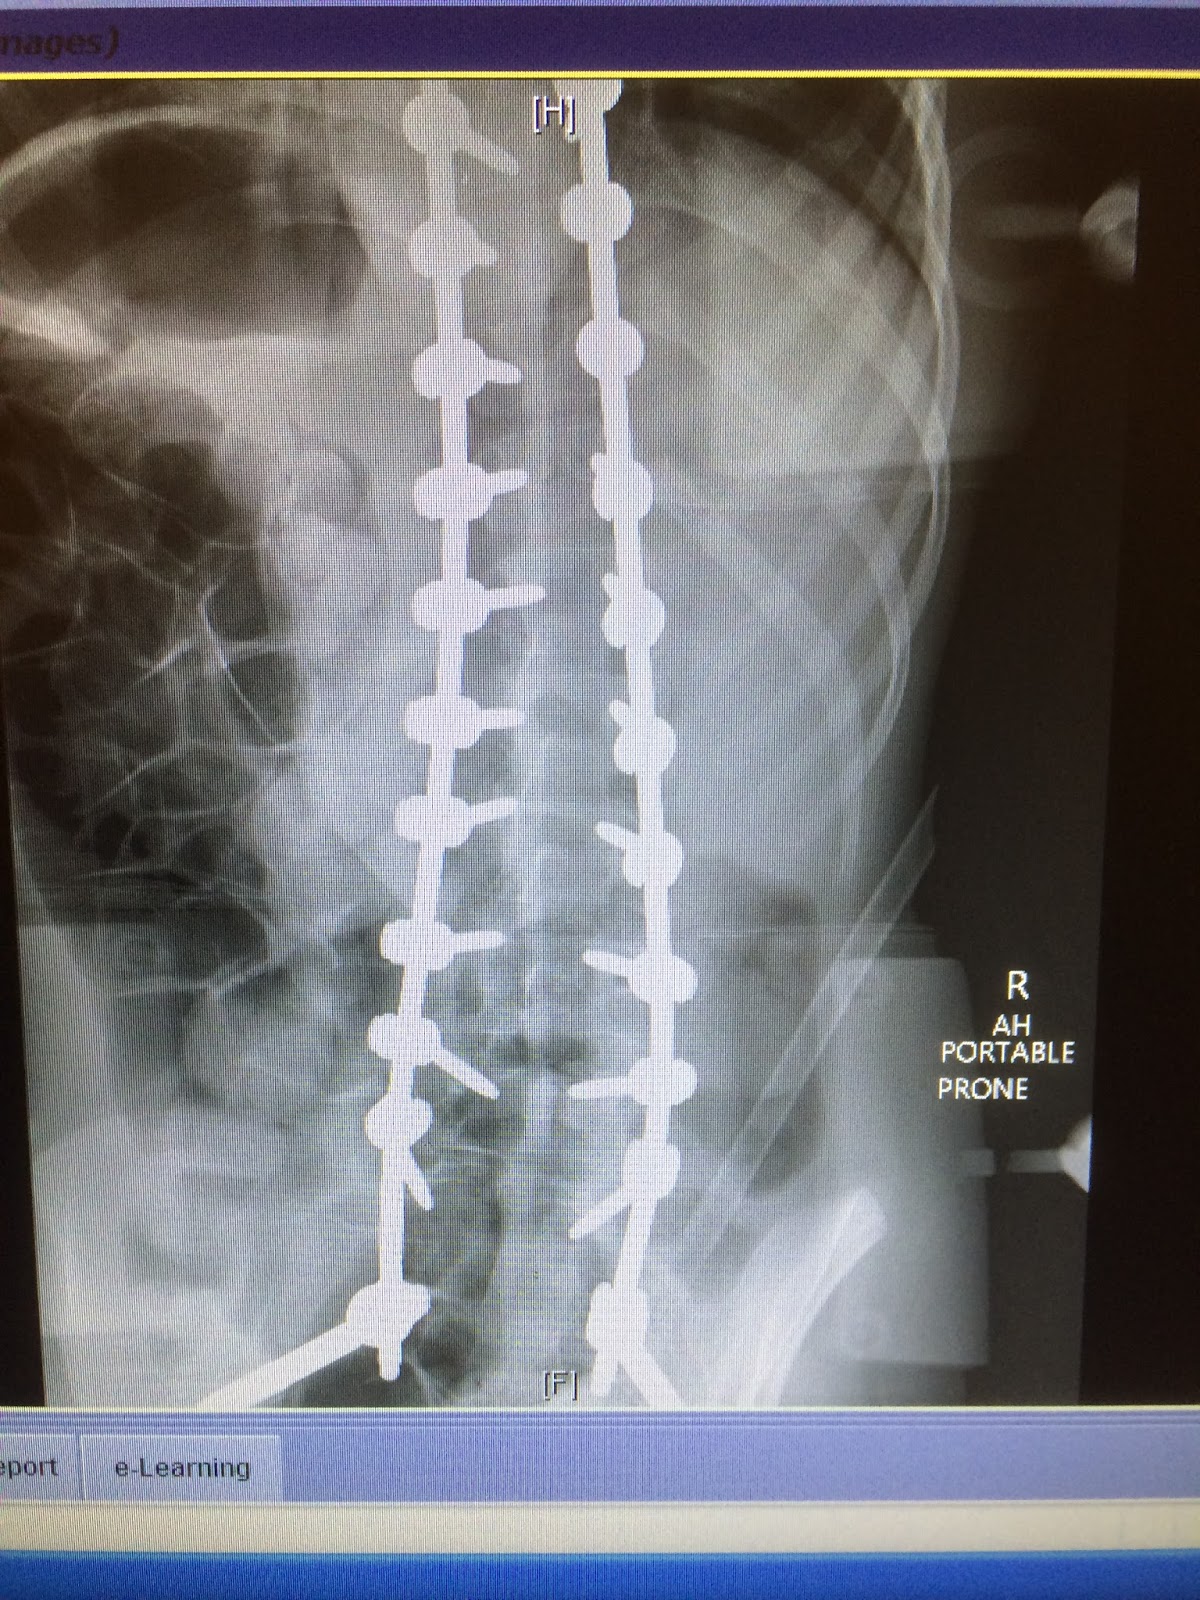

Then it was like I don’t know 11 AM and we were in a room with Dr. White where he was excited to show us her before and after X Ray, surgery was successful!

![]() |

| post surgery.. what curve? |

Her pre surgery curve was 70 degrees sitting. She went from a 50 to a 70 in a short amount of time and was only getting worse. Surgery wasn’t a cosmetic or really optional choice, she needed to be straightened to have a healthy body. She is now very straight.